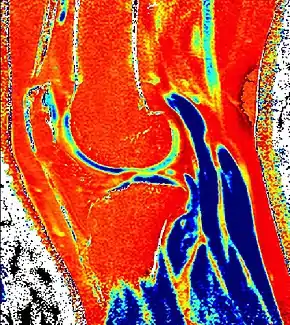

Delayed gadolinium-enhanced magnetic resonance imaging of cartilage

Delayed gadolinium-enhanced magnetic resonance imaging of cartilage or dGEMRIC measures the fixed-charge density and relative proteoglycan content of articular cartilage using the spin-lattice relaxation time or T1 relaxation time.[1] Current research is investigating the clinical application of dGEMRIC as a quantitative tool for monitoring cartilage function in diseased or repair cartilage.[2]

![]() dGEMRIC T1 Map of knee cartilage | |

| Purpose | measures relative proteoglycan content of articular cartilage |